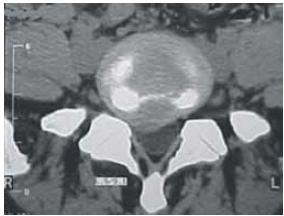

Um empregado de uma fábrica de móveis com 47 anos de idade queixa-se, há algum tempo, de lombalgia, mas continua trabalhando normalmente. Certo dia, teve queda de cima de um caminhão e não conseguiu mais andar devido à dor na região lombar e no membro inferior à direita; ficou em repouso por uma semana, mas continuou com os sintomas álgicos. Voltou ao serviço médico quando realizou novo exame físico, sendo constatadas algumas alterações. O médico solicitou uma tomografia computadorizada (TC) da coluna lombar, cuja imagem é reproduzida abaixo, e o encaminhou ao neurologista.

A TC de coluna lombar evidencia lesão compatível com hérnia discal como causa dos sintomas referidos pelo paciente. Tal patologia é mais comum nos segmentos torácicos e lombares.